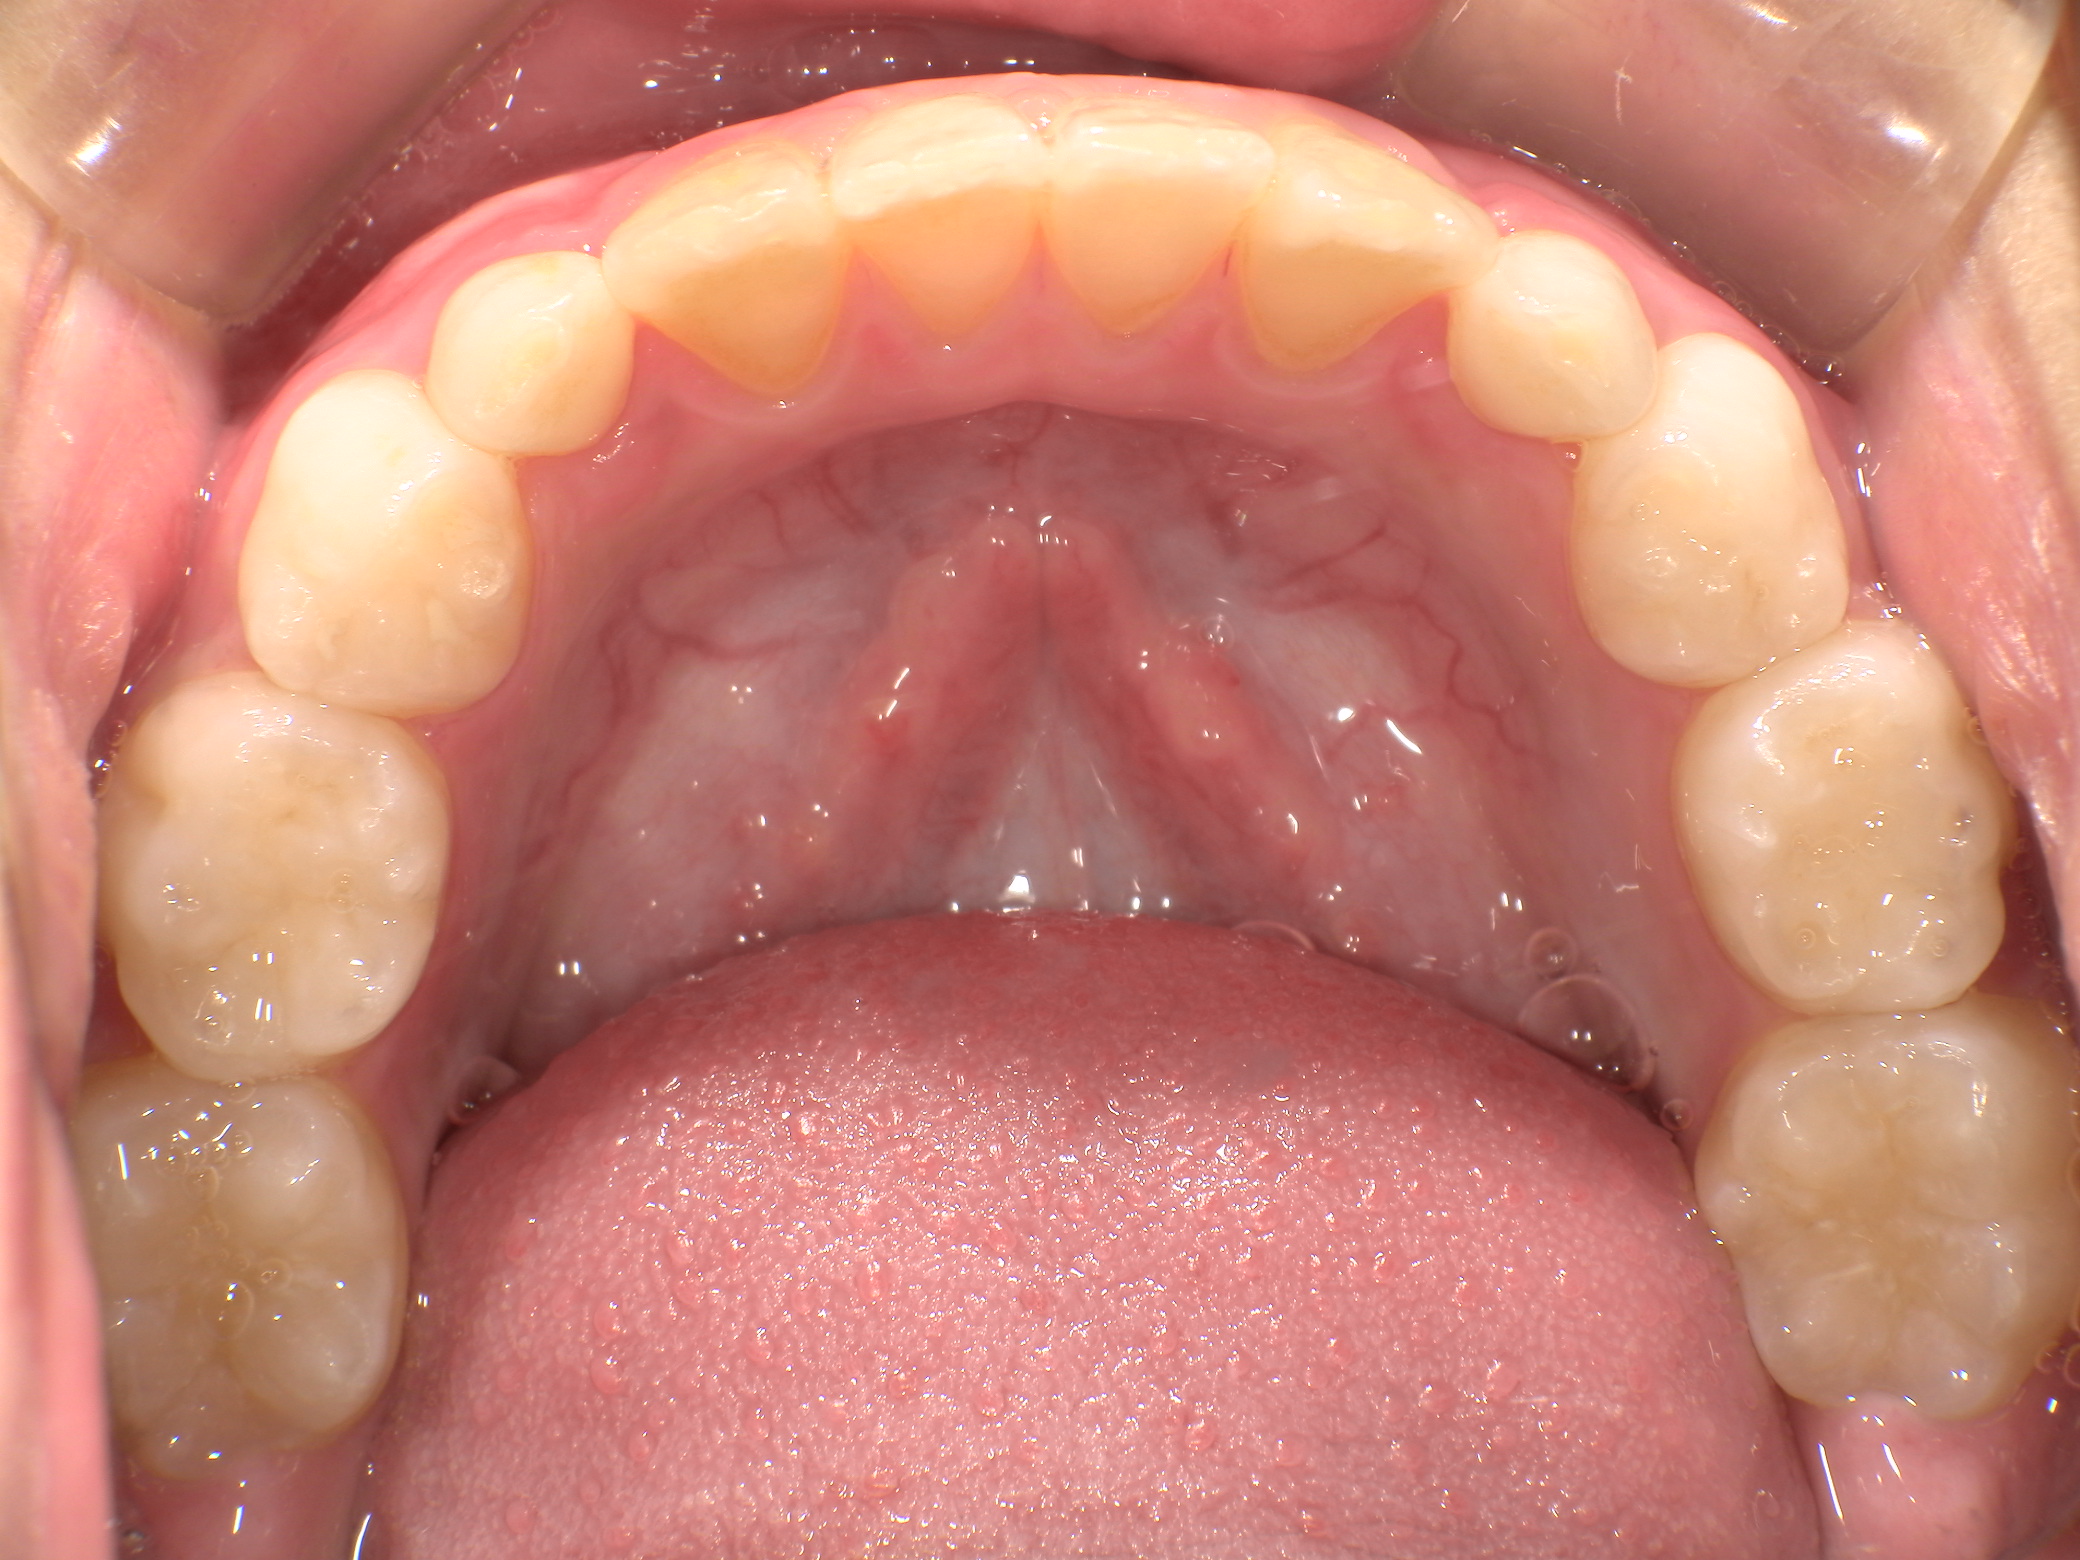

早期矯正治療 叢生症例①

主訴 | 歯の生えるスペース不足が懸念され、歯列の乱れ(叢生)を整えるために来院された患者様です。 |

---|---|

診断結果 | 7歳1か月の男児。 叢生の進行が見込まれると診断されました。 |

治療内容 |

|

治療後の経過 | 1年3か月の動的治療を通じて、上下顎の歯列が改善されました。 治療終了後は3〜4か月に一度の定期検診を継続しており、本格矯正治療の開始時期を判断していく方針です。 |

治療期間 | 動的治療期間:1年3か月 通院回数:11回 |

治療費用 | 420,000円(税別) |